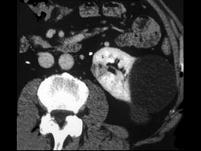

问题 女,45岁,左侧腰背部隐痛不适,请根据所示图像,选择最可能诊断 ( )

选项 A、左肾小肾癌 B、左侧小肾癌合并单纯性肾囊肿 C、左侧单纯性肾囊肿 D、左侧多发性肾囊肿 E、左肾未见异常

答案 B